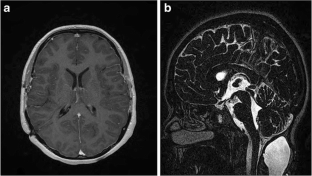

Fig. 2